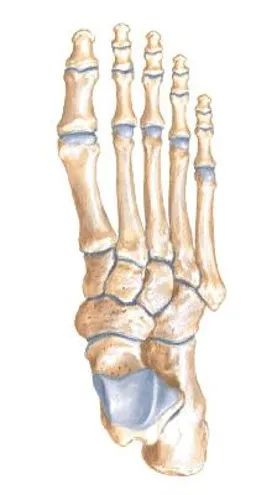

解剖

整个关节结构可以划分为三个柱:

• 内侧柱:第一跖骨和内侧楔骨

• 中柱:第2、3跖骨和中外侧楔骨

• 外侧柱:第4、5跖骨和骰骨

第二跖骨基底部深入到3个楔骨形成的马蹄形凹槽中,在跖跗关节的稳定性中起重要作用。

跖骨的基底及楔骨、骰骨形成一拱形结构,也有较好的稳定作用。

软组织的稳定性:1、跖骨颈部由骨间横韧带将相邻的跖骨连接在一起;2、跖骨基底部除第1、2跖骨外也有骨间横韧带连接;3、侧副韧带和关节囊;腓骨长肌腱、胫前肌腱、和胫后肌腱提供动力稳定。

第1、2跖骨基底间无韧带相连,使第一跖骨具有一定的活动度,也是一应力薄弱部位。

Lisfranc韧带在内、中柱的稳定性中起重要的作用,手术从背侧不能将其修复,只能使用内固定使其达到稳定。

足底韧带的强度明显大于足背侧 ,维持足弓。受到外力易发生背侧损伤或脱位。

除第一跖骨外,其余四个跖跗关节均为向外的斜面,与中轴倾斜约为60°,在矢状面上,向前下方倾斜。各跖骨基底呈上宽下窄倒三角形。